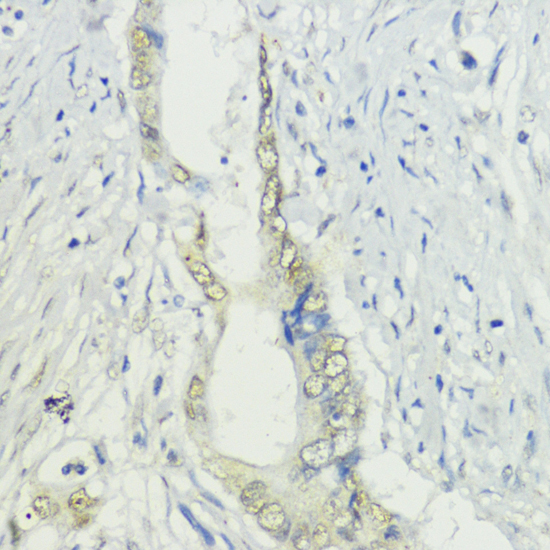

Immunohistochemistry of paraffin-embedded human mammary cancer using BAZ2A at dilution of 1:200 (40x lens).

,

Immunohistochemistry of paraffin-embedded human colon carcinoma using BAZ2A at dilution of 1:200 (40x lens).

Immunohistochemistry of paraffin-embedded mouse testis using BAZ2A at dilution of 1:200 (40x lens).